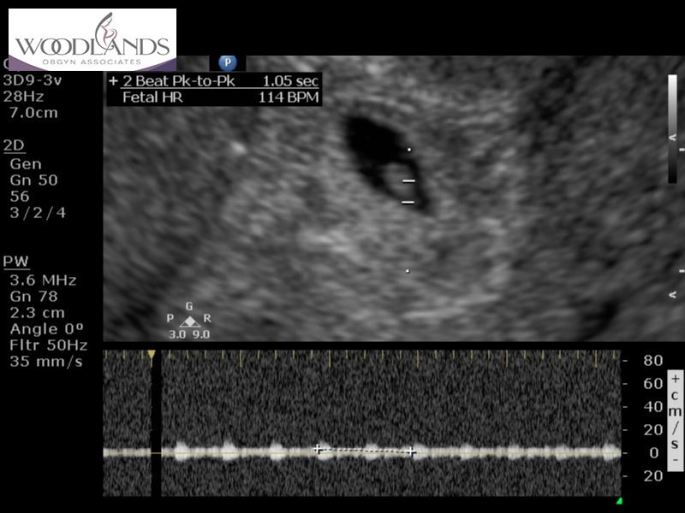

oh.my.gosh. There it was. A little bean. HR and all. Coming in at 114bpm. Amazing to have a heart beat that soon. I was only registered 5w,4d. They kept thinking 7 weeks but I insisted that the date of conception does not go on that projected date and they finally listened. We see this little RAINBOW again on Monday, September 23rd. Stay tuned. I’m praying it’s still there. Still beating will all of Gods amazing force and glory. And…didn’t multiply. Haha!!!